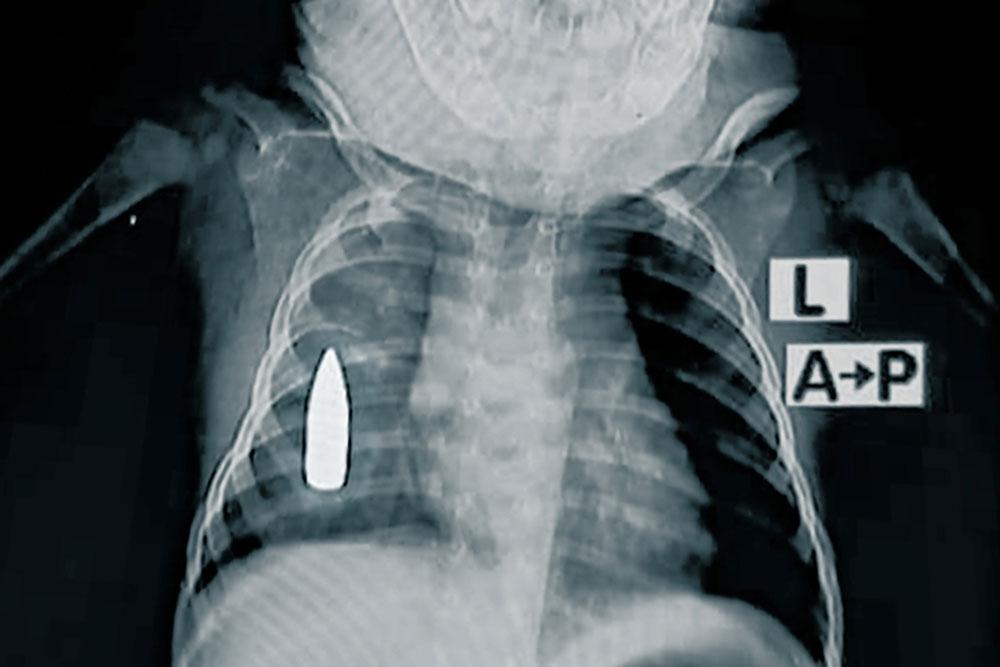

Radiographie de Riyad. L'enfant de 18 mois a été touché à la poitrine par une balle perdue alors qu'il faisait une sieste à Khartoum. © MSF

Riyad, 18 mois, est l'un des 314 enfants soignés pour des blessures par balle ou par explosion cette année. « Riyad a été amené aux urgences après avoir été touché au côté droit par une balle perdue alors qu'il faisait la sieste dans la maison familiale », explique le Dr Moeen1 , responsable de l'équipe médicale de MSF. « L'équipe médicale a tenté de le stabiliser pendant quatre heures. En raison de l'importante perte de sang, il y avait une chance sur deux pour qu'il ne survive pas à l'opération ».

L'équipe a réussi à arrêter l'hémorragie, mais la balle est restée logée dans sa poitrine. L'hôpital ne dispose pas de capacités chirurgicales avancées, en partie à cause d'un blocage systématique de l'envoi de matériel chirurgical depuis octobre 2023. Il est également très difficile d'envoyer des patients hors de la zone, car les routes sont soit détruites, soit beaucoup trop dangereuses.